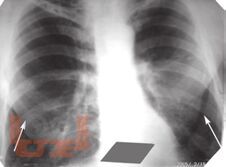

В настоящей монографии подробно описаны и проиллюстрированы изменения легких, сердца и костной системы при различных патологических состояниях в пульмонологии, кардиологии и ревматологии. Сопоставлены клиническая и рентгенологическая картины при различный нозологических формах проявления многих заболеваний. Все представленные результаты рентгенологических исследований верифицированы и подтверждены клинически. Монография предназначена для врачей-рентгенологов, пульмонологов, кардиологов и ревматологов, а так же врачей других специальностей, занимающихся диагностикой и лечением органов грудной клетки.